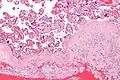

Acute choriodeciduitis, with neutrophils seen in the chorion and decidua.